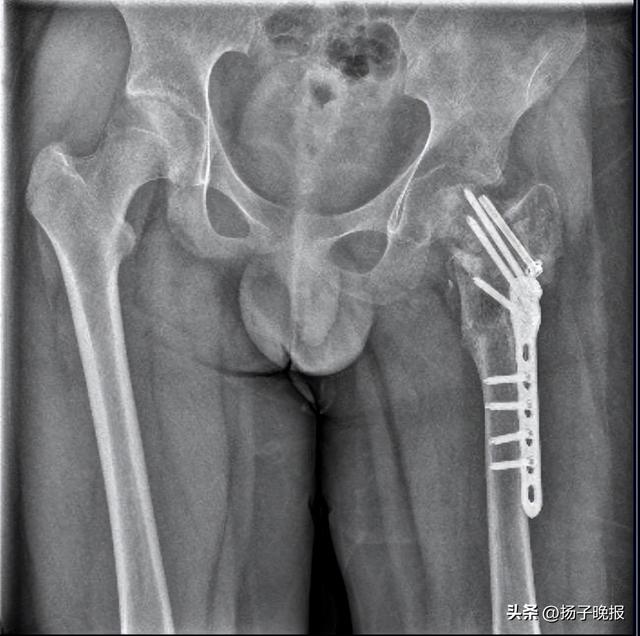

▲小武左股骨陈旧性骨折,打了钢针、钢板 图据受访人

7月,晋江市公安局对小武被故意伤害一案立案侦查。随后,晋江市公安局对小武进行了人体损伤程度鉴定,8月29日出具的《鉴定意见通知书》显示,小武三个部位不同程度损伤,其中,“左髋部重伤二级,胸部轻伤一级,双下肢轻微伤”,同时,其左股骨打了钢针、钢板。